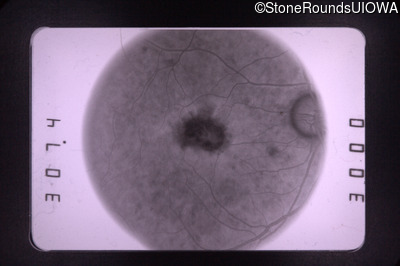

Fluorescein Angiography - Right - 20/70 -1 cc

Exemplar